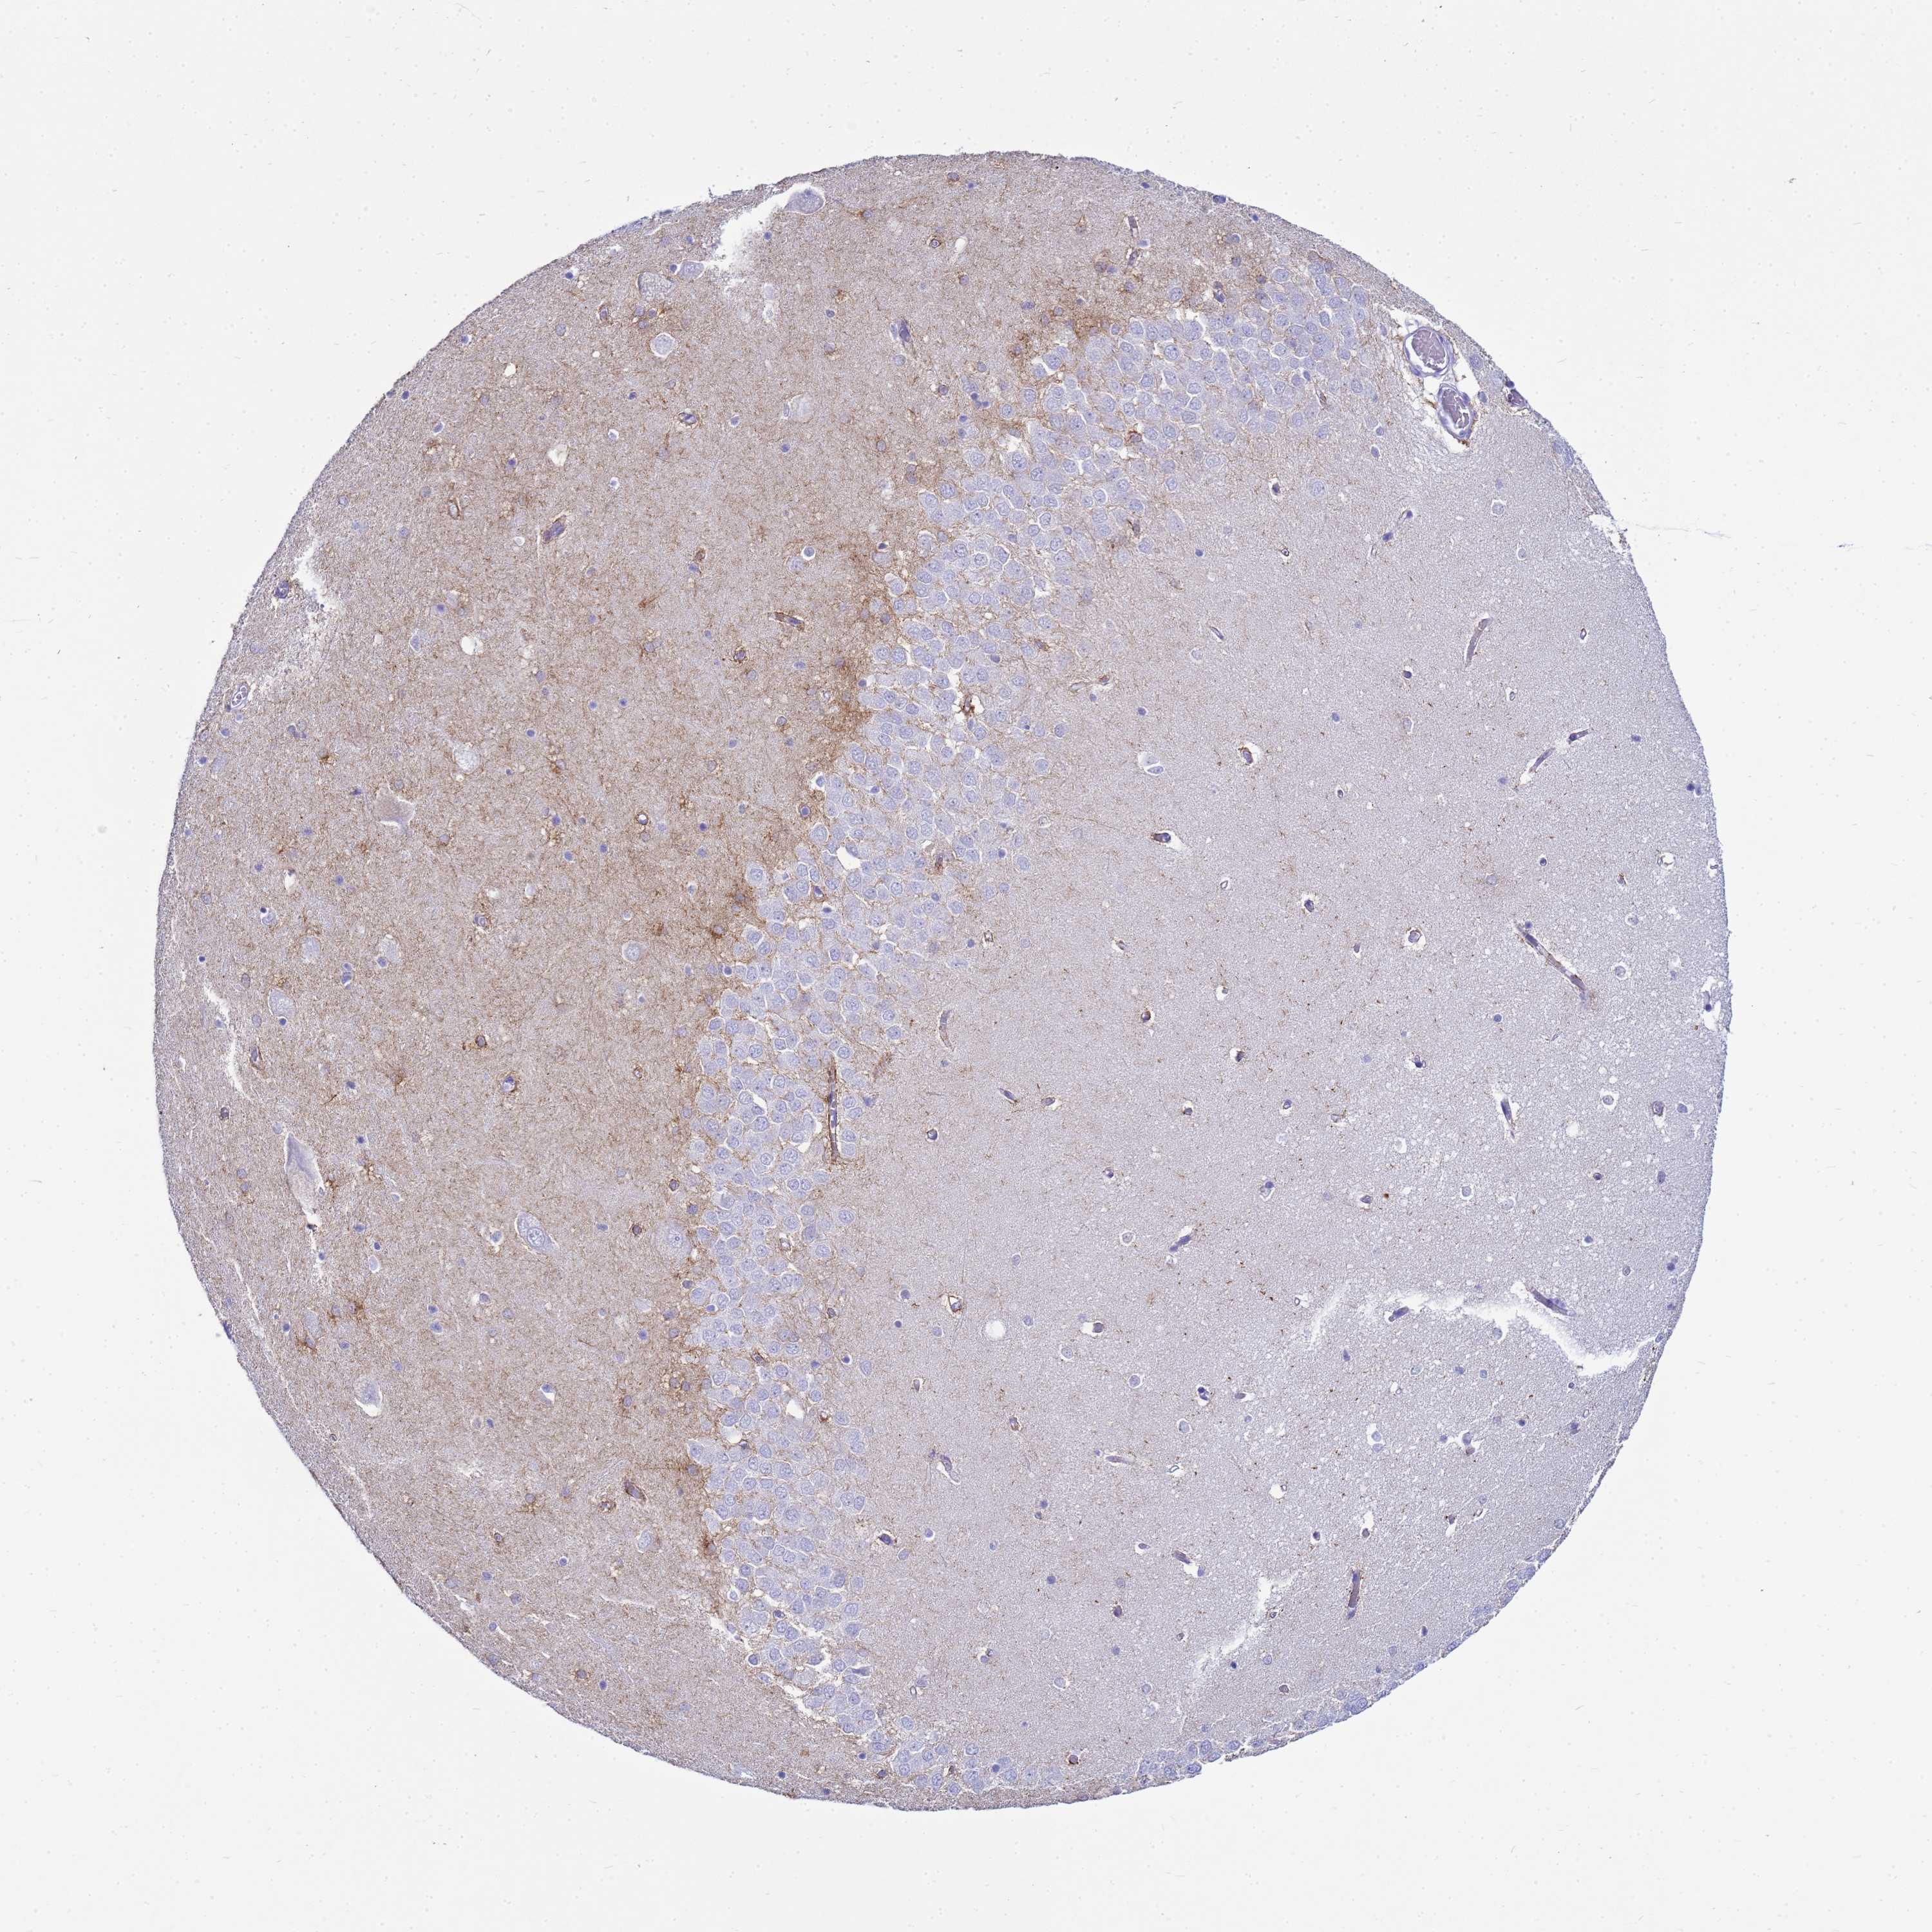

Antibody staining in the annotated cell types in the current human tissue is reported as not detected, low, medium, or high. This score is based on the staining intensity and fraction of stained cells.